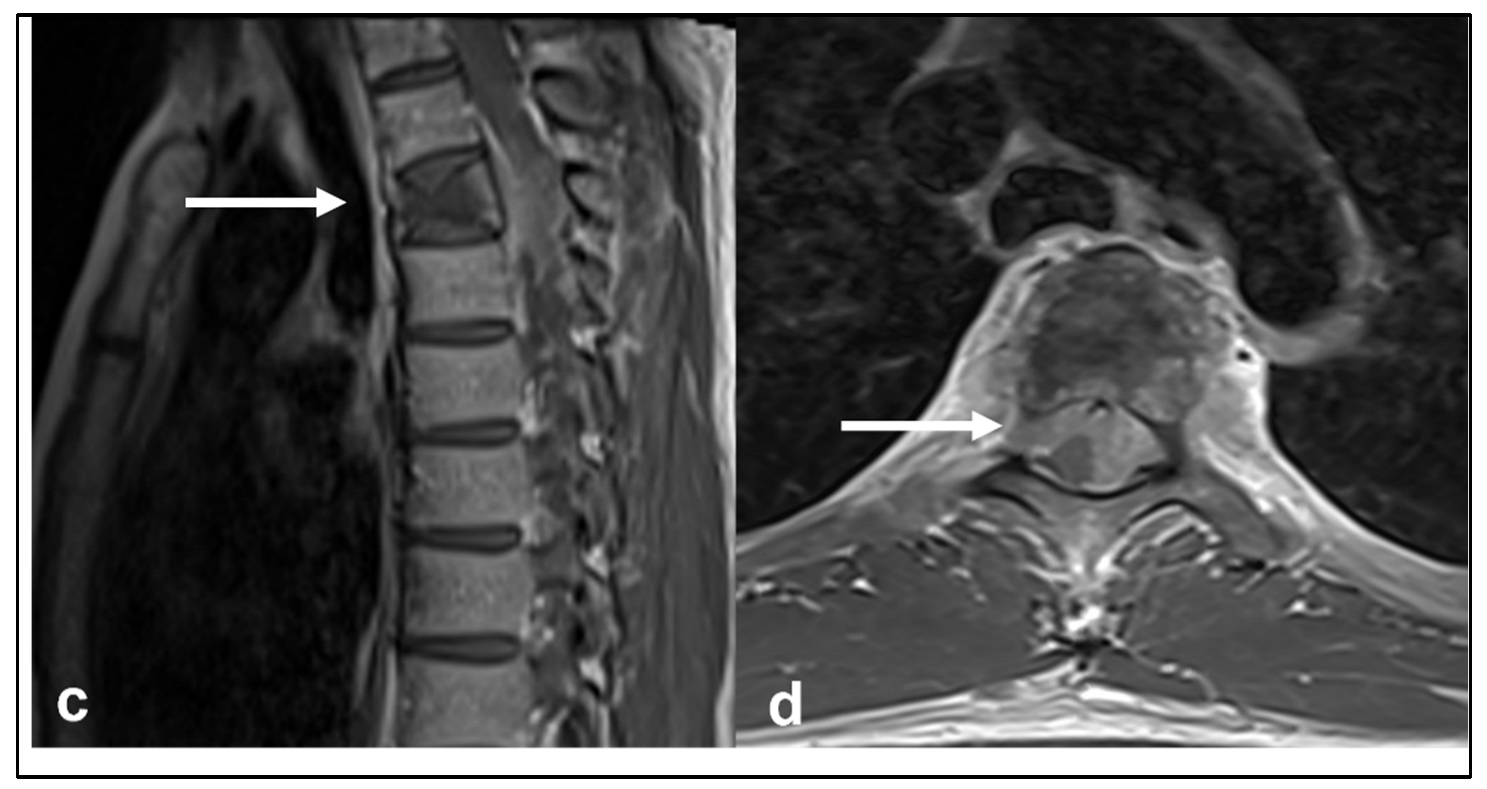

| Chordoma | Low attenuation lytic lesion. | Loculated high T2 signal mass, usually with extra-osseous soft tissue component. High T1 signal due to haemorrhagic and calcified components. |